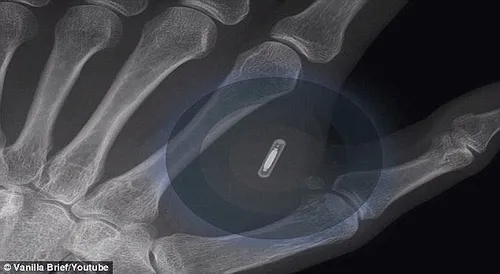

Een Zweeds bedrijf heeft microchips geïmplanteerd bij haar werknemers. Ze kunnen daarmee het kopieerapparaat gebruiken, hun lunch afrekenen en beveiligde deuren openen. Uiteindelijk moeten zo'n 700 werknemers van het Epicenter high-tech kantorencomplex in Stockholm de chip met persoonlijke informatie in hun hand krijgen. De chips gebruiken radiogolf identificatie en zijn zo groot als een rijstkorrel. Ze worden al gebruikt in bijvoorbeeld openbaar vervoer-kaarten. Hannes Sjoblad, die werkzaam is bij het bedrijf dat de chips implanteert, vertelt: 'We gebruiken deze technologie al, maar dan met pasjes en pincodes. Zou het niet veel handiger zijn als je alleen nog maar je hand nodig hebt?' Hij vervolgt: 'We willen deze techniek begrijpen voor de grote bedrijven naar ons toekomen en zeggen: iedereen moet een chip. Je krijgt dan de Facebook of de Google chip.'